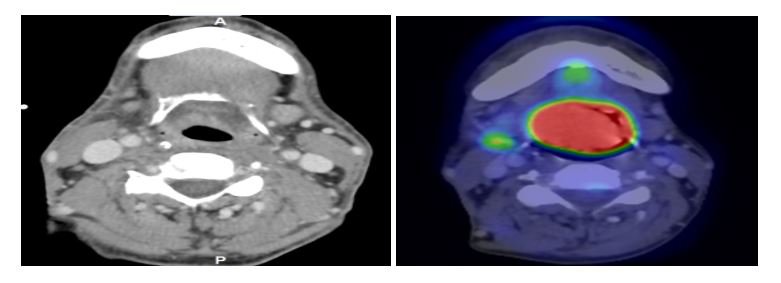

Bước 6: Theo dõi và đánh giá bệnh nhân trong, sau xạ trị: Theo dõi và đánh giá bệnh nhân trước, trong và sau các buổi xạ VMAT. Sau đó mỗi 6 tháng, bệnh nhân được đánh giá lâm sàng, chụp MRI/CT/PET-CT.

Bệnh nhân Ung thư Họng miệng T4N1M0